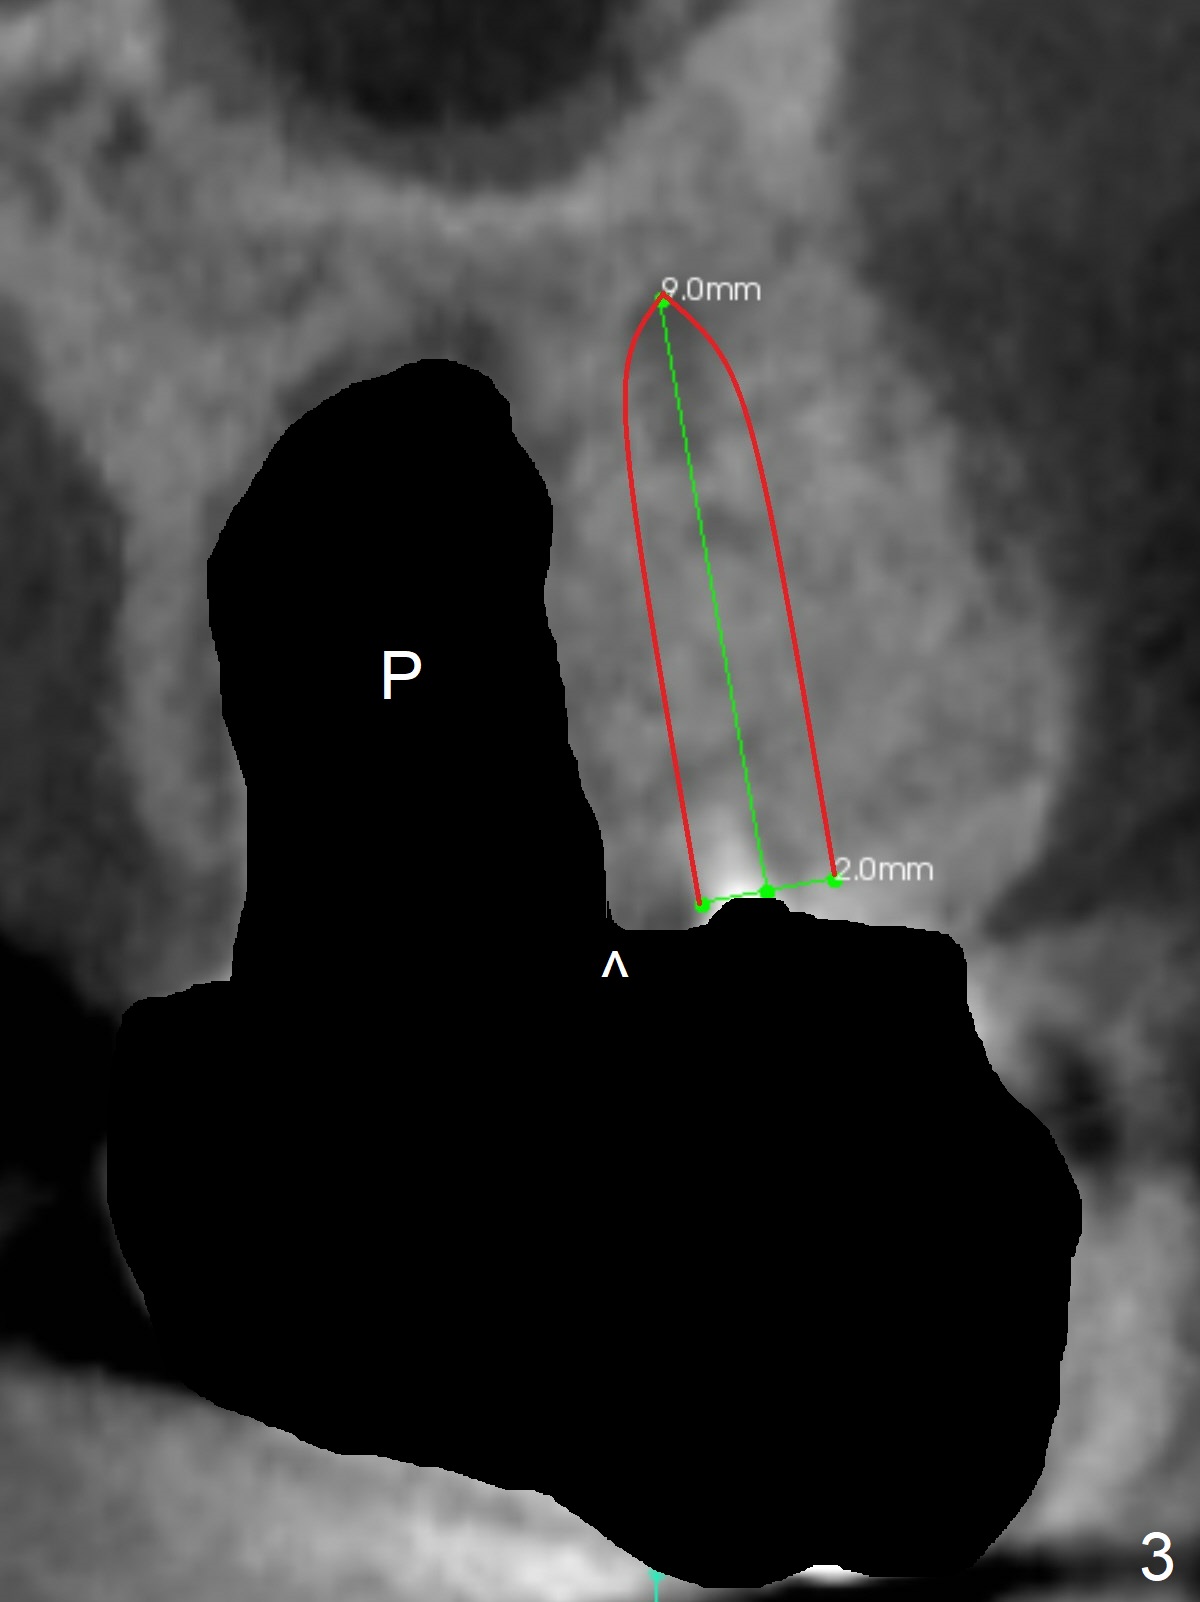

A 53-year-old man cannot chew on the left side with distal abscess in spite of RCT for #14 (* in Fig.1,2 (taken 11 ad 21 months postop, respectively)). After extraction (Fig.3 (CBCT coronal section) black area), start osteotomy with 2 mm drill (red outline) in the septum buccal to the palatal (P) socket). Following 2 mm drill removal (Fig.4), use 4.3 mm Magic Drill (red outline) for ~ 9 mm. When the osteotomy is being done, the osteotomy most likely shifts palatal (Fig.5 arrow) because of thin bone palatally. When the MD is removed (Fig.6), use Magic Sinus Lifter (Fig.7 pink) for sinus lift (arrow). The implant is to be 5x11 mm or larger. Because of the distal defect (Fig.1,2), start osteotomy mesially. Take Alginate impression before surgery for possible orthodontic treatment. Since bone density is high, use higher voltage and longer time for X-ray.